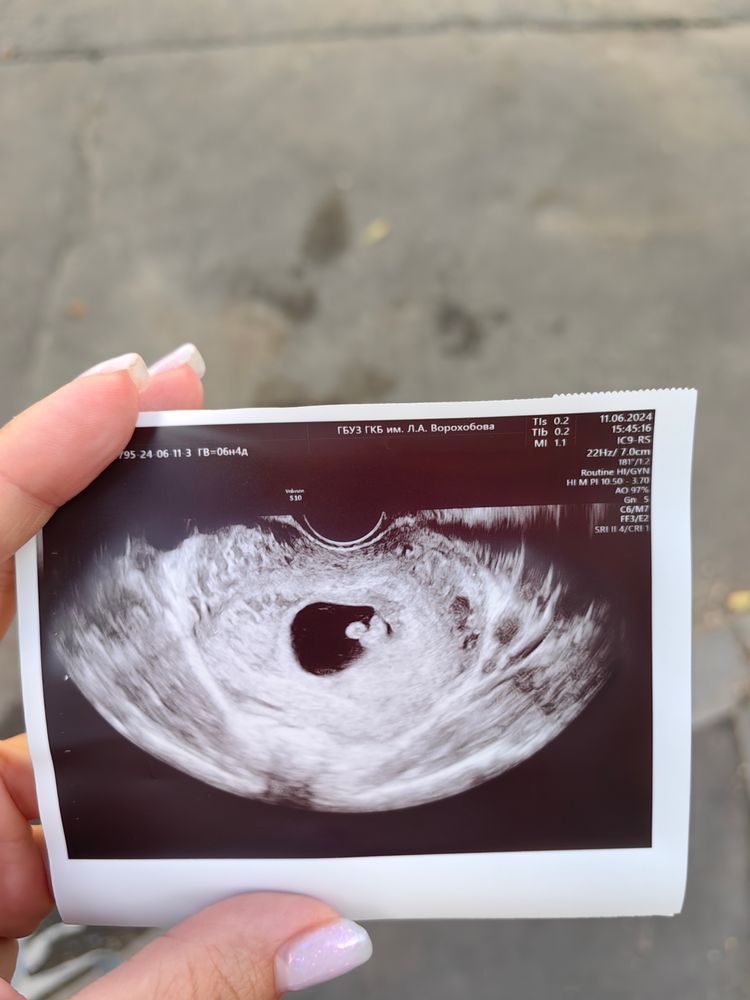

Санкт-Петербург

Подскажите пожалуйста кто у меня) (трансвагинально) 7 недель

0

Privet malysh, скорее всего девочка